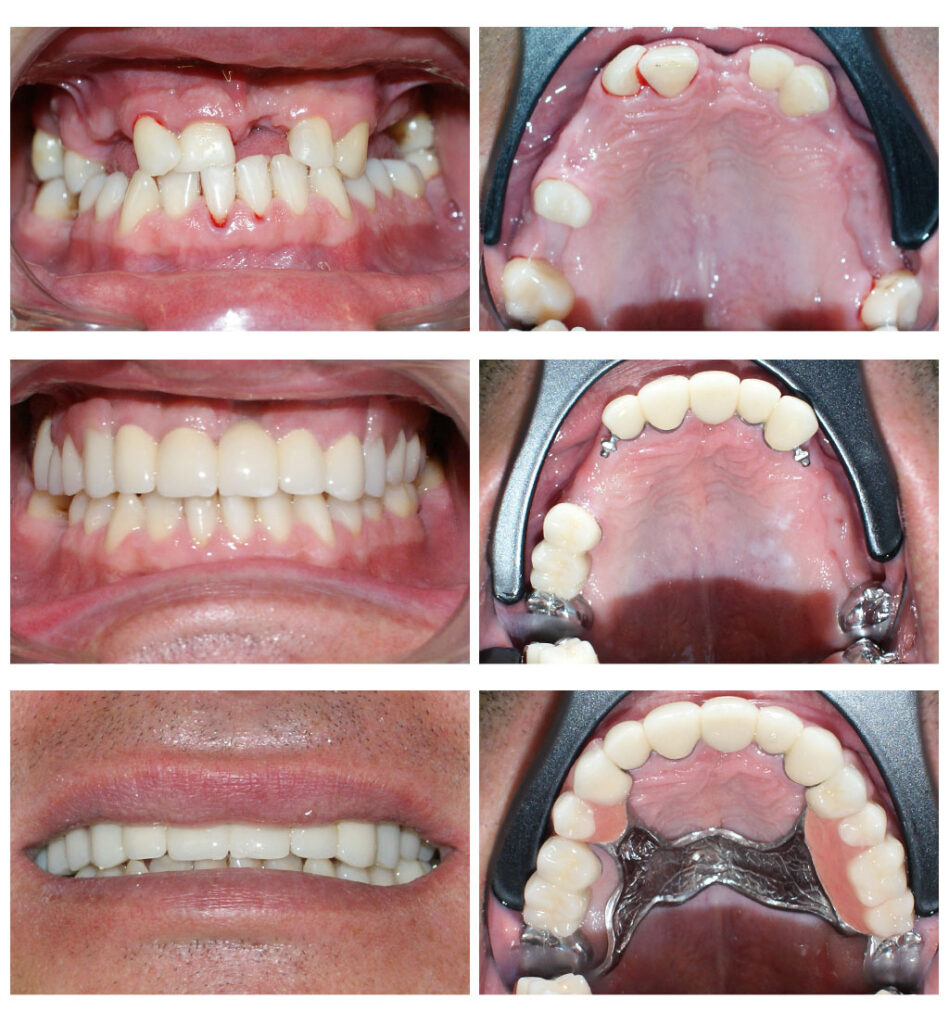

Un caz de o dificultate estestică majoră pe care l-am rezolvat cu succes împreună cu tehnicienii noștri. Am reușit să salvăm toți dinții deși erau destul de mult afectați și ulterior să îi îmbracăm cu coroane solo. Cromatica coronițelor este atât de potrivită încât în final nu se diferențiază de dinții naturali printre care sunt intercalate

Lucrare fixată pe dinți împreună cu proteză scheletată mobilizabilă = soluția de lux pentru dinți puțini

Proteza telescopată și proteză scheletată aplicate pe dinții tratați corect! Execuția riguroasă oferă stabilitate excelentă.